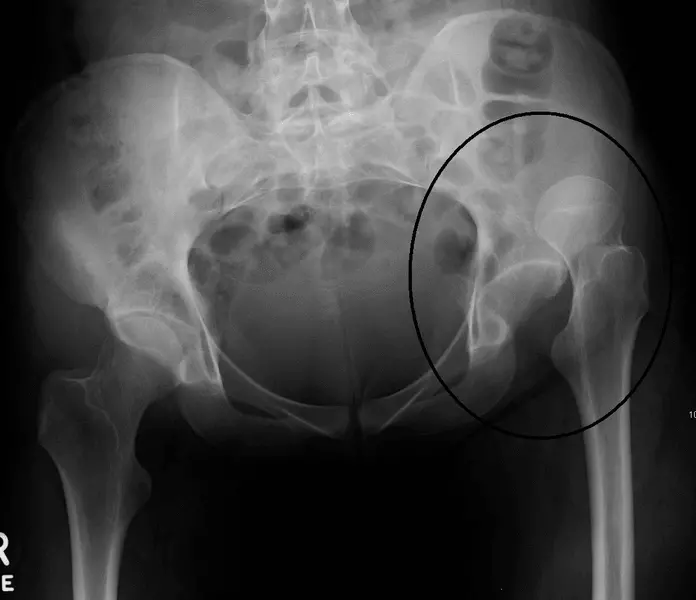

Image - An X-ray of a superior hip dislocation

Creative commons source by James Heilman, MD [CC BY-SA 4.0 (https://creativecommons.org/licenses/by-sa/4.0)]